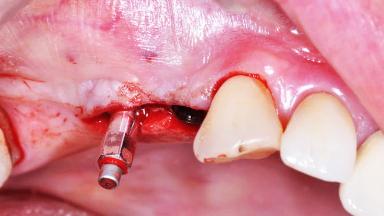

Surgical treatment of a 68-year-old female patient who experienced failure of her conventional bridge in the right maxilla. After removal of the compromised abutment teeth and a healing period of 6 weeks, a sinus floor elevation procedure using the lateral window technique and a composite graft to correct the insufficient bone height is carried out.

Two dental implants are placed in the same surgical session. The case concludes with the presentation of the final fixed dental prosthesis with a distal cantilever unit.

The 1-year follow-up radiographs demonstrate successful sinus floor elevation and stable bone crest levels around both implants, leading to a favorable long-term prognosis of the implant-supported prosthesis.